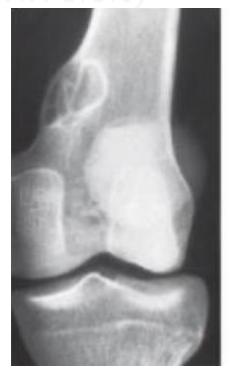

Q8/ What is the type of fracture shown in these pictures?

- A- Salter harris fracture II